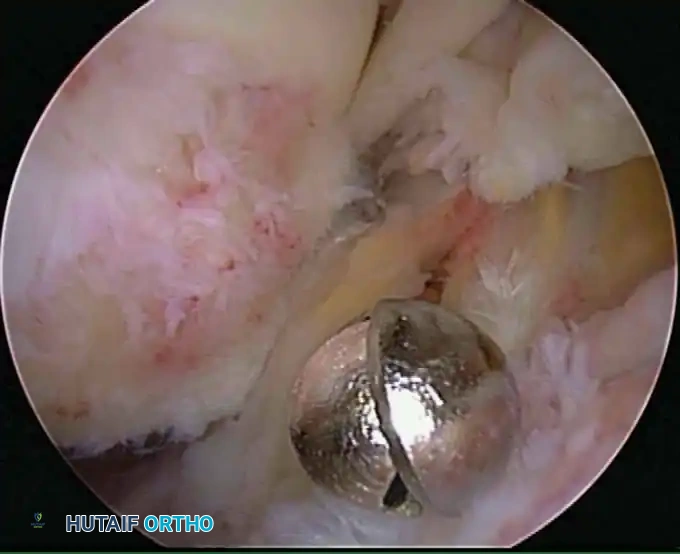

* Identification and extraction of loose bodies: Particularly those residing in the posterior recess, which are notoriously overlooked during open procedures.

Modern arthroscopy relies heavily on suture anchors (biocomposite or all-suture constructs) and advanced arthroscopic knot-tying or knotless techniques. The ability to pass sutures through retracted, fibrotic tissue and secure them under appropriate tension without strangulating the microvascular supply is the hallmark of a master arthroscopist.